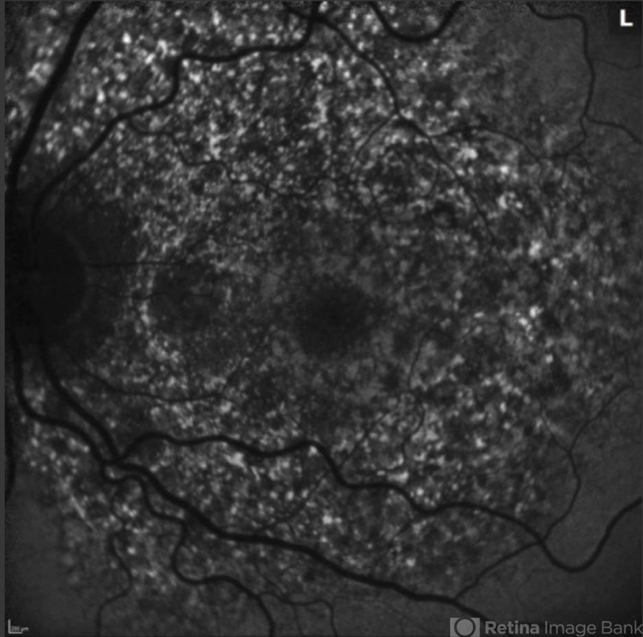

- Pentosan Macuopathy

- pentosan sulfate

- Scanning laser ophthalmoscope

- 56-year-old woman with prior long term use of pentosan for cystitis. She self discontinued the pentosan 1 year ago. Imaging shows patch RPE atrophy OU with a ¾ DA patch of geo atrophy OS. Autofluorescence shows punctate hyperautoflouresence and FA shows staining of RPE mottling with reticular features.